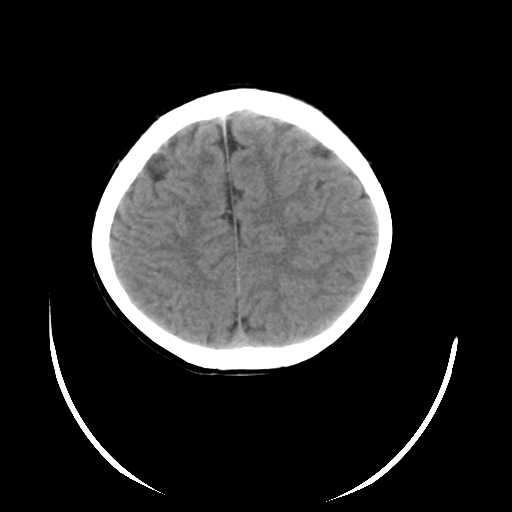

女,6岁,头痛、呕吐一天。